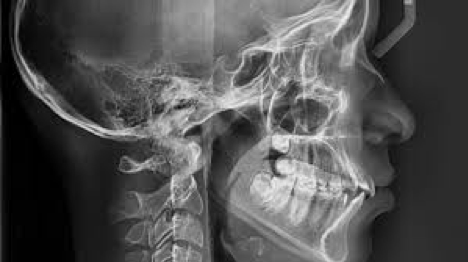

En un mundo que cambia constantemente, la nueva tecnología digital ha revolucionado la forma de analizar las estructuras dentales y maxilares, permitiéndole al odontólogo detectar caries o enfermedades bucales de forma inmediata y facilitando la discusión de casos con otros colegas.

Aunque la finalidad de una evaluación a través de radiografías sigue siendo la misma, la disposición de equipos DIGITALES permite al odontólogo reducir significativamente la exposición de sus pacientes a la radiación.

En lugar de utilizar películas radiográficas, hoy en día la forma ideal de captar la radiación que pasa a través de los tejidos es mediante el uso de sensores digitales o radiovisógrafos, que utilizan “softwares” especializados para proyectar la imagen del área tomada, en un computador.

3. Calidad y precisión: con las imágenes computarizadas se pueden magnificar áreas de interés y ver en detalle tanto los dientes como los tejidos duros y blandos dela boca. La claridad de estas imágenes es mucho mayor y facilita la identificación de lesiones, fracturas e imperfecciones en los tejidos.

Las Radiografías dentales son esenciales para un diagnóstico acertado… los nuevos EQUIPOS DIGITALES disponibles tanto para radiografías intra orales como extraorales (ej.panorámica), permiten al odontólogo planificar tratamientos con mayor eficacia y precisión, así como velar por la seguridad de sus pacientes y no exponerlos a radiación innecesaria.